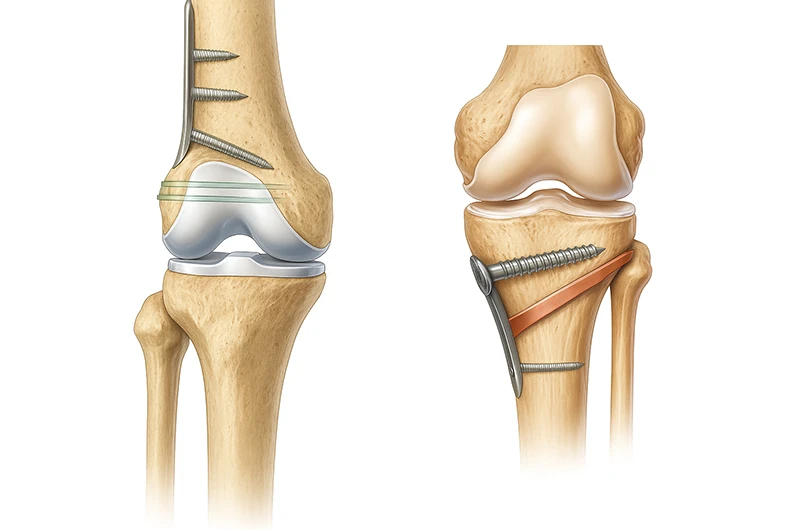

Artrose Avançada

Uma das indicações mais comuns é a artrose em estágio avançado. A artrose é o desgaste da cartilagem que reveste as articulações, levando ao atrito entre os ossos, causando dor, inchaço e rigidez. Quando a cartilagem se desgasta completamente, a reconstrução, muitas vezes através da artroplastia (substituição da articulação por uma prótese), pode trazer um alívio significativo da dor e restaurar a mobilidade. Isso é comum em articulações como o quadril e o joelho.

Lesões Graves nos Ligamentos e Cartilagem

Outra situação em que a reconstrução pode ser necessária são lesões graves nos ligamentos ou na cartilagem que não cicatrizam adequadamente com tratamentos não cirúrgicos. Por exemplo, lesões complexas no joelho envolvendo múltiplos ligamentos ou grandes áreas de dano na cartilagem podem se beneficiar de técnicas de reconstrução para restaurar a estabilidade e a função da articulação.

Fraturas Complexas

Em casos de fraturas complexas que afetam as superfícies articulares, a reconstrução osteoarticular pode ser essencial para garantir que a articulação se cure de forma alinhada e funcional, prevenindo o desenvolvimento de artrose pós-traumática.